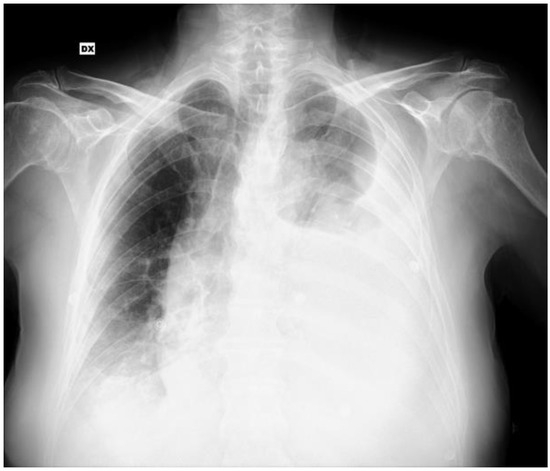

2. Case Report